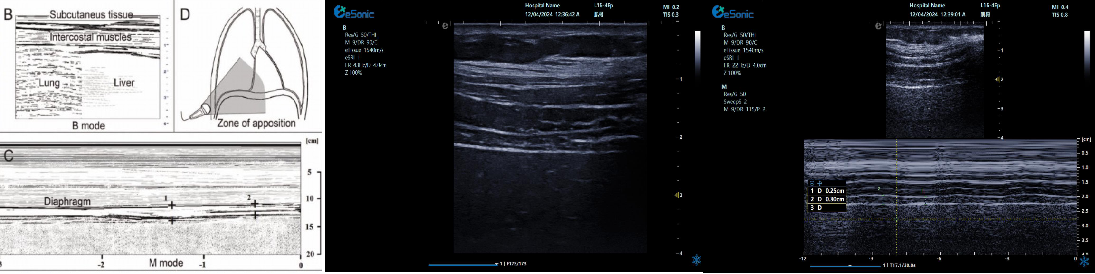

膈肌超

评估内容:膈肌移动度、膈肌厚度、增厚率。

评估意义:判断病人膈肌功能,呼吸功能,脱机前后评估等

常用检查模式:B、M

检查探头:凸阵、线阵

对超声设备要求:M型、解剖M型;测量快速准确;有专用的测量包

膈肌厚度检查

image.png

探头:高频线阵探头

部位:放置于腋前线与腋中线,7/8肋间或8/9肋间,沿肋间隙放置,观察和测量膈肌的厚度。

功能:M型超声,膈肌测量包

膈肌厚度变化

膈肌厚度测量

呼气末膈肌厚度正常值为2.0-3.5cm

膈肌活动度检查

探头:低频探头

部位:放置在腋前线或锁骨中线与肋缘交界处,启用M模式取样线垂直于膈肌,观察和测量膈肌运动幅度。

功能:M超,膈肌测量包

膈肌活动度测量